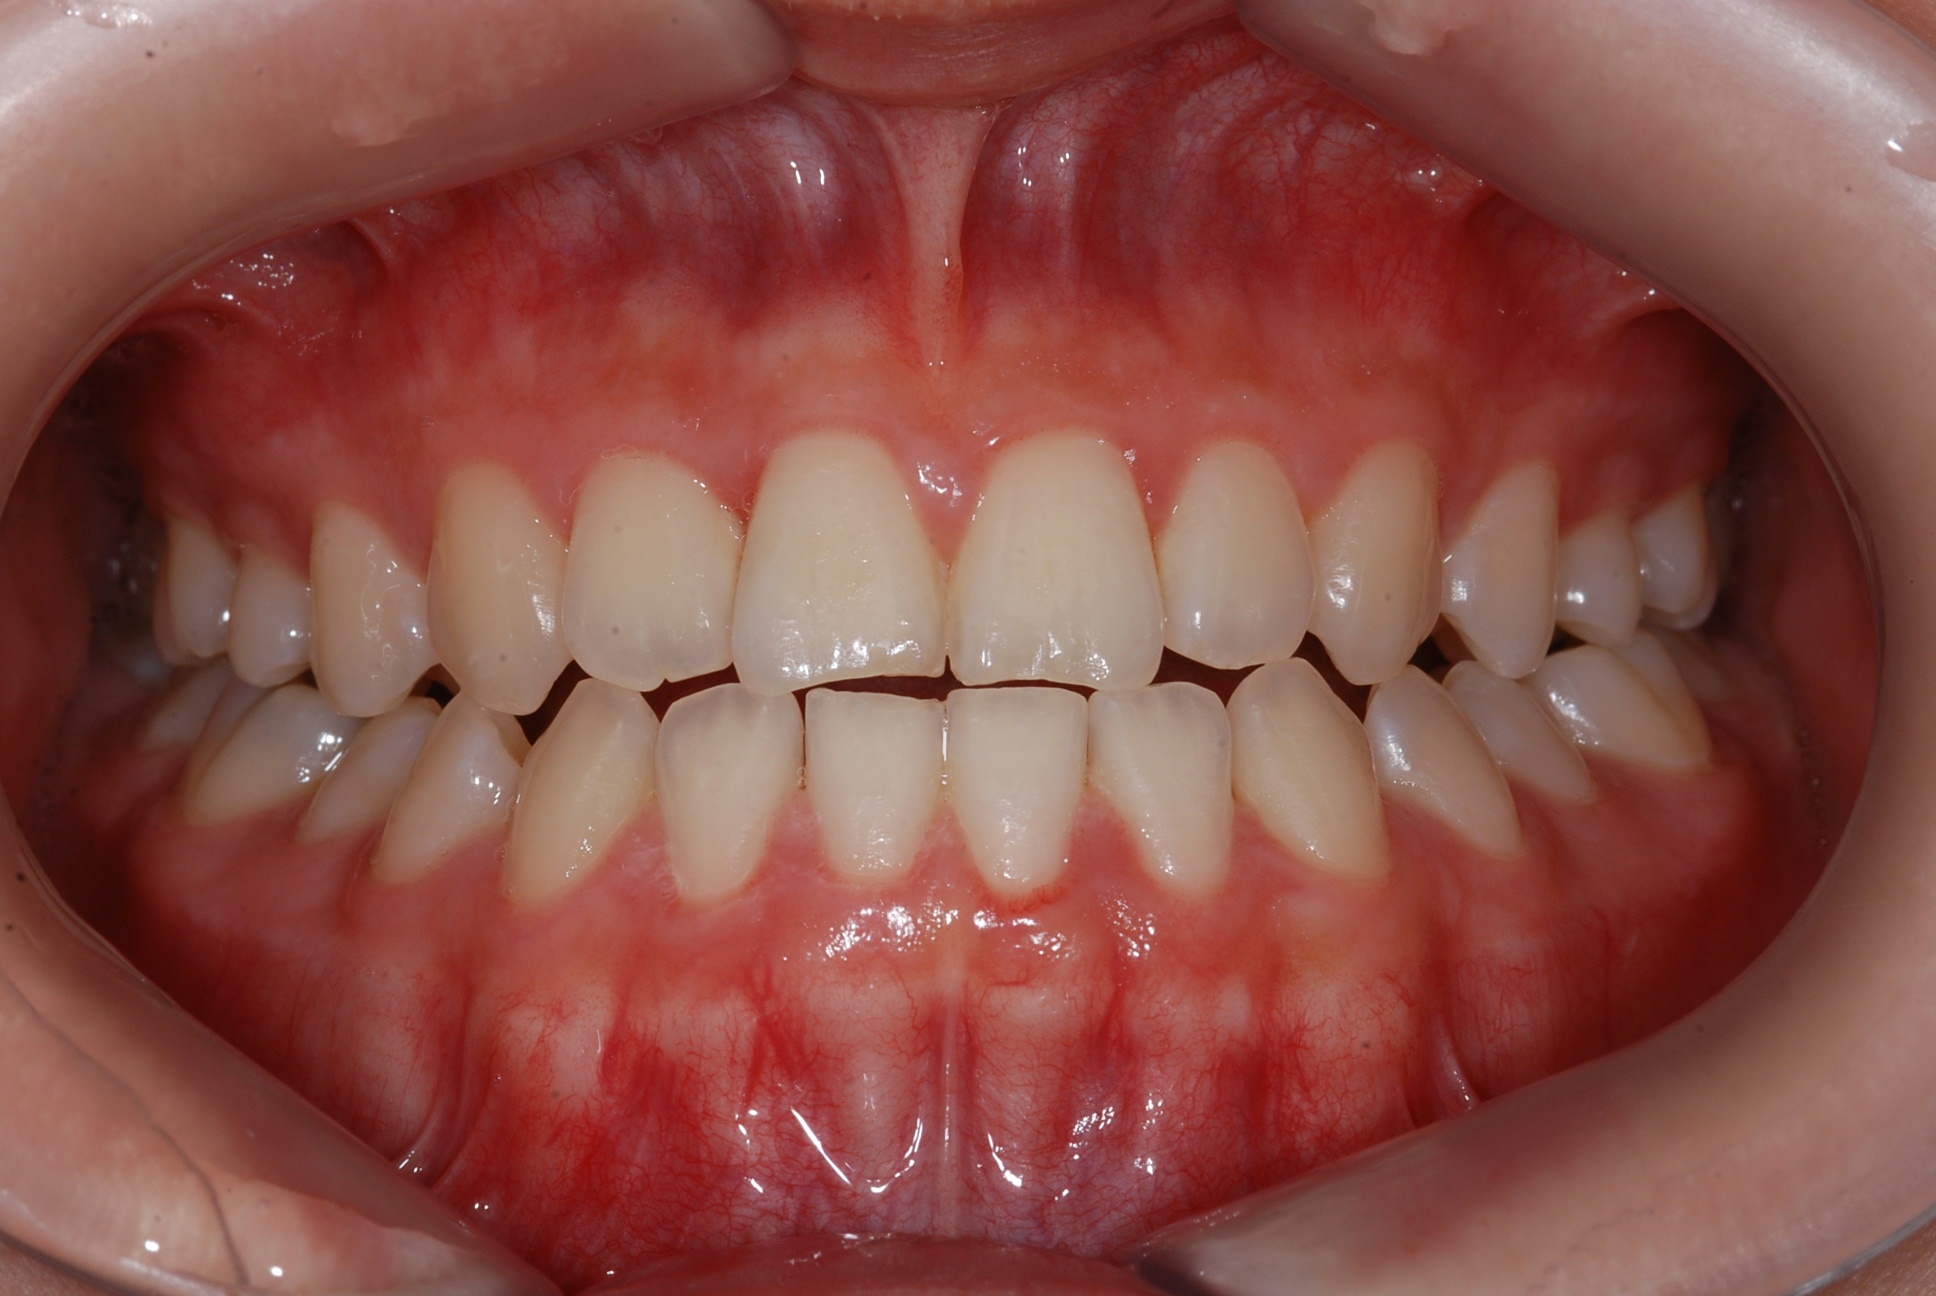

치료 후 사진입니다.